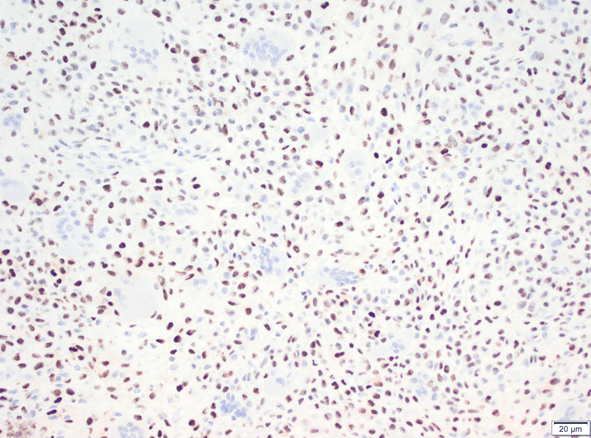

使用抗BRAF V600E兔单克隆抗体克隆RM8对福尔马林固定和石蜡包埋的甲状腺癌组织进行免疫组织化学染色。